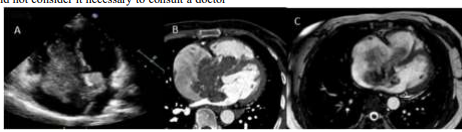

Figure: Myxoma of the left atrium

A 53-year-old female patient with no history of chronic diseases. She was admitted to the emergency department with complaints of tachycardia and dizziness. Laboratory examination: all parameters are within normal limits. ECG: tachycardia. According to ECHO-CG (see Figure. A), CT angiography (see Figure.), MRI (see Figure. C): a space-occupying biatrial lesion with invasion into the right ventricle (biatrial myxoma?)

As a clinical example, our own case of observation of a patient with a left atrial myxoma is presented. Patient A., 44 years old, nurse. Height 167, weight 70 kg. No bad habits. During a medical examination on 30.04.2019, atrial fibrillation was detected for the first time on the electrocardiogram (ECG), due to which the patient was taken to the hospital. The patient complained of weakness, shortness of breath during physical exertion (climbing to the 2nd floor), palpitations, associated this with detraining, and was not examined. According to the patient, rhythm disturbances appeared over the past 3-4 months. Concomitant diseases: chronic venous insufficiency, varicose veins of the lower extremities, compensation stage. In the anamnesis, it is noteworthy that over the past 3 months, the patient noted the appearance of short-term subfebrile temperature, in the general blood test (CBC) an increase in ESR to 25 mm / hour, did not consult a doctor, took antipyretics. During an examination in the hospital during echocardiography according to the standard method from 05/17/2019, a volumetric round hyperechoic mobile formation (myxoma) of an oval shape, measuring 3.6 x 2.3 cm, is visualized. The tumor has a stalk, is fixed in the area of the oval fossa, mobile, with prolapse through the mitral valve into the cavity of the left ventricle, fixed on a stalk in the projection of the open oval window (figure). Ejection fraction is 65%, right atrium 42/49 mm, left atrium 51/55 mm, right ventricle 25/41 mm, left ventricle: EDS/ESR 43/23 cm, EDV/ESR 81/19 ml, IVS 16/9 mm, LVP 10/15 mm, aorta 32 mm, aortic valve is tricuspid, gradient 2.98, orifice area 3.3 mm, mitral valve cusps are unchanged. Tricuspid valve - grade 1 regurgitation. Mean pulmonary artery pressure is 31 mm Hg. The patient was hospitalized for surgical treatment with a diagnosis of left atrial myxoma, permanent atrial fibrillation, type